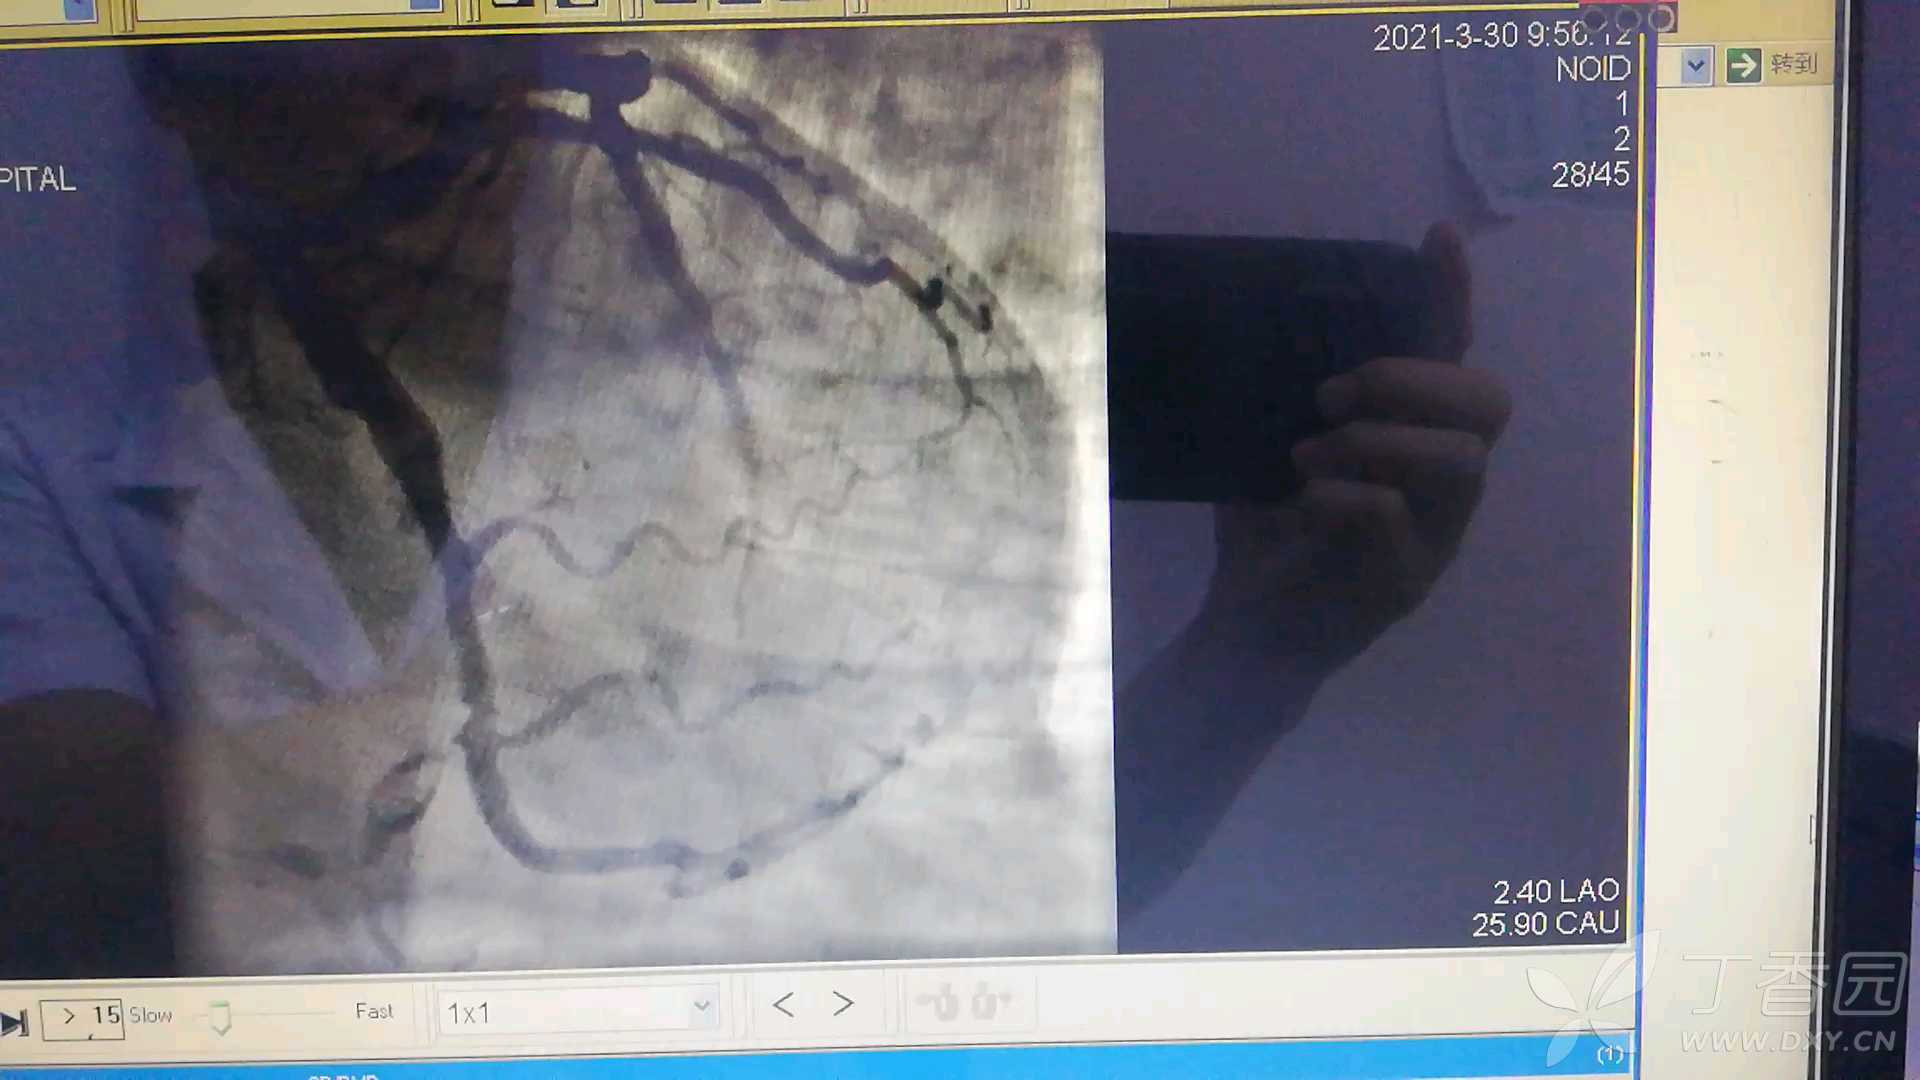

病例回旋支巨大血栓 动脉瘤